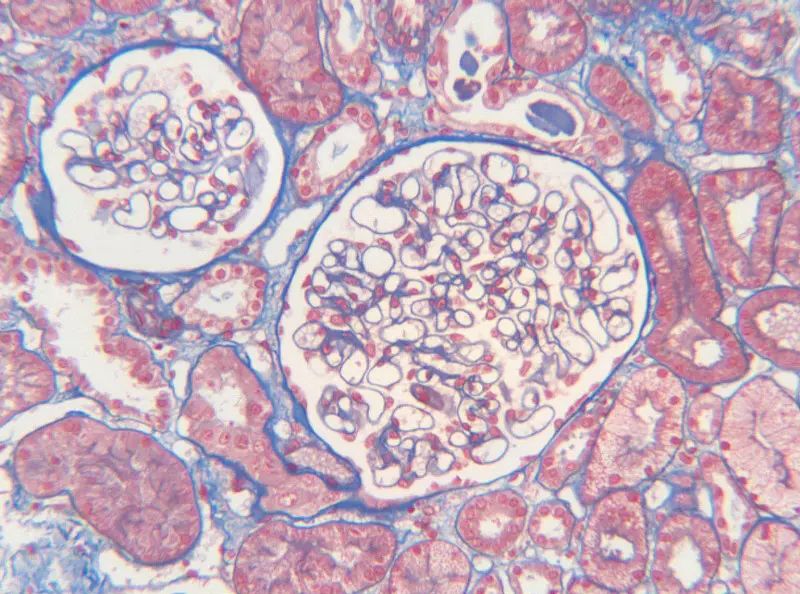

首先,讓我們深入探討MASSON染色的原理。MASSON染色的原理與陰離子染料分子的大小和組織的滲透性密切相關(guān)。染料的分子量決定了其穿透組織的能力:小分子量的染料更容易穿透結(jié)構(gòu)致密、滲透性較低的組織,而大分子量的染料則更傾向于進入結(jié)構(gòu)疏松、滲透性較高的組織。在MASSON染色中,由于肌纖維間隙較小,而膠原纖維間隙較大,因此小分子量的麗春紅染料更容易滲透進入肌纖維并使其呈現(xiàn)紅色,而大分子量的苯胺藍染料則主要進入膠原纖維并使其呈現(xiàn)藍色或綠色。

MASSON染色的陽性意義在于,它能夠幫助研究人員區(qū)分膠原纖維和肌纖維,從而觀察病變組織中纖維結(jié)締組織的增生和分布。當MASSON染色結(jié)果呈現(xiàn)陽性時,通常意味著局部組織中存在膠原纖維的增生。這種增生可能是由于局部皮膚出現(xiàn)炎癥或組織增生等病理 過程所導(dǎo)致的。因此,MASSON染色的陽性結(jié)果可以作為判斷組織纖維化程度的一個重要指標。